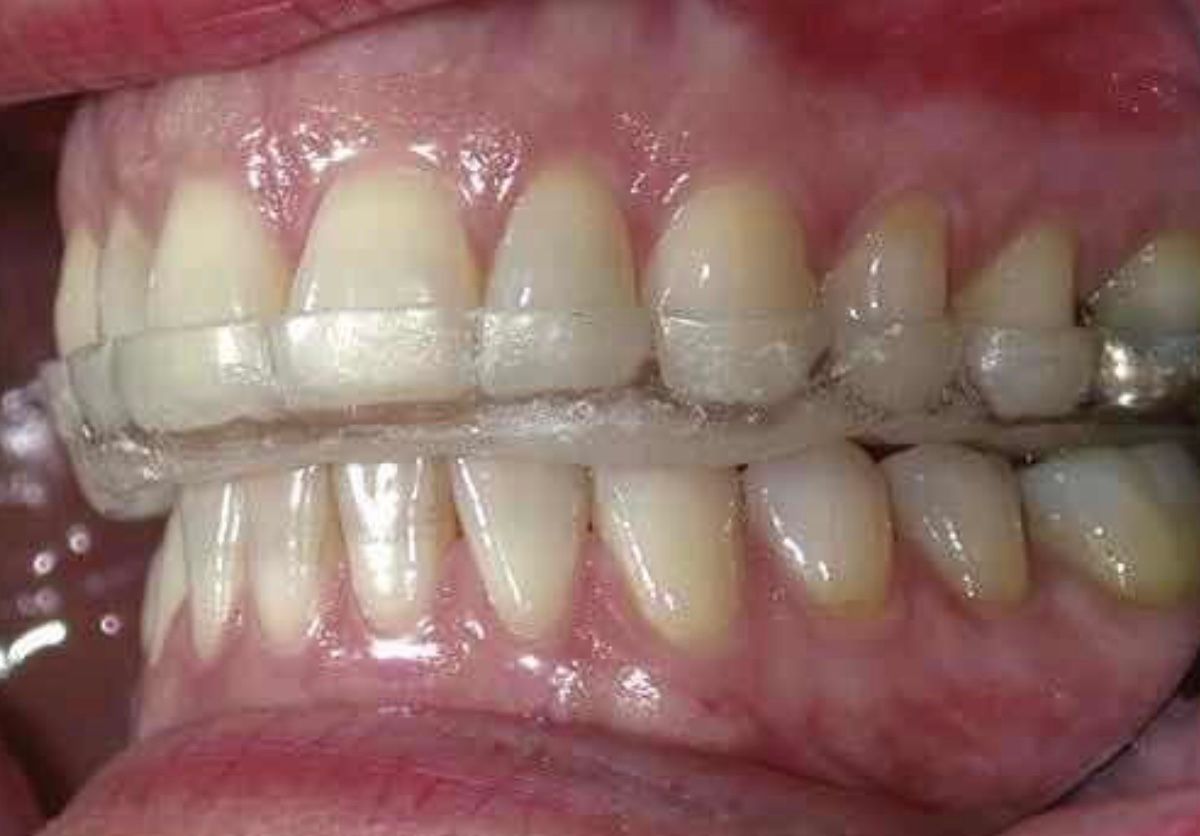

Desgaste dental

El desgaste dental es un padecimiento muy frecuente el cual requiere de eliminar el estimulo que origina el desgaste y restaurar la dentadura mediante diversos procedimientos ya sea resinas de alta estética o coronas de zirconia.

Se requiere una valoración con radiografías digitales y fotografías intraorales.